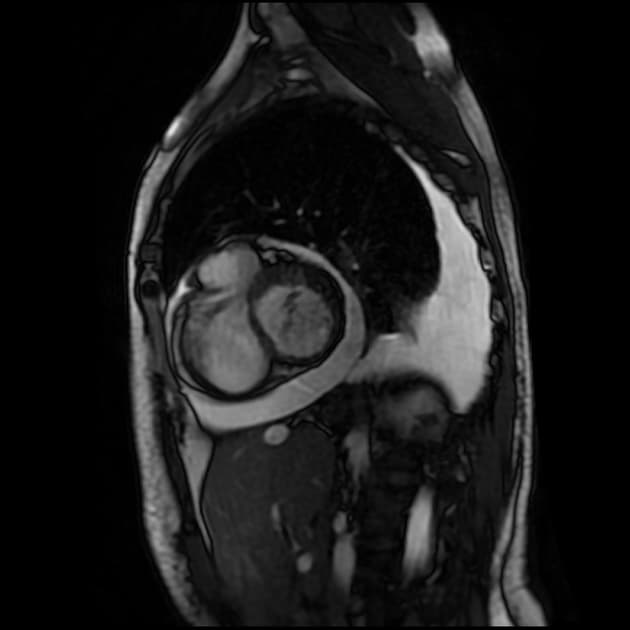

Short axis Cine SSFP

MRI•Short axis Cine SSFP•1 / 25

- Không thấy hình ảnh (no evidence of) vỡ thất, nhưng hình ảnh động (cine images) cho thấy thành trước giữa thất trái bị rối loạn vận động (dyskinetic), phồng ra ngoài trong thì tâm thu.

- Trên hình STIR, đoạn cơ tim tổn thương tăng tín hiệu (hyperintense), phù hợp với phù (edema).

- Vị trí tổn thương là bất thường, vì thường thì các đoạn đỉnh (apical segments) bị ảnh hưởng trong bệnh lý này. Tuy nhiên, ba kiểu hình ảnh khác biệt đã được ghi nhận: hai thất (biventricular), giữa thất (mid-ventricular – như trường hợp này), và đoạn đáy (basal).

- Trên cộng hưởng từ (MRI), các phát hiện điển hình gồm phù cơ tim (myocardial edema) và không có thiếu máu cục bộ (ischemia) hay xơ hóa (fibrosis), điều này được chứng minh bằng việc không tăng quang ở thì muộn sau tiêm gadolinium (lack of enhancement at late gadolinium imaging).